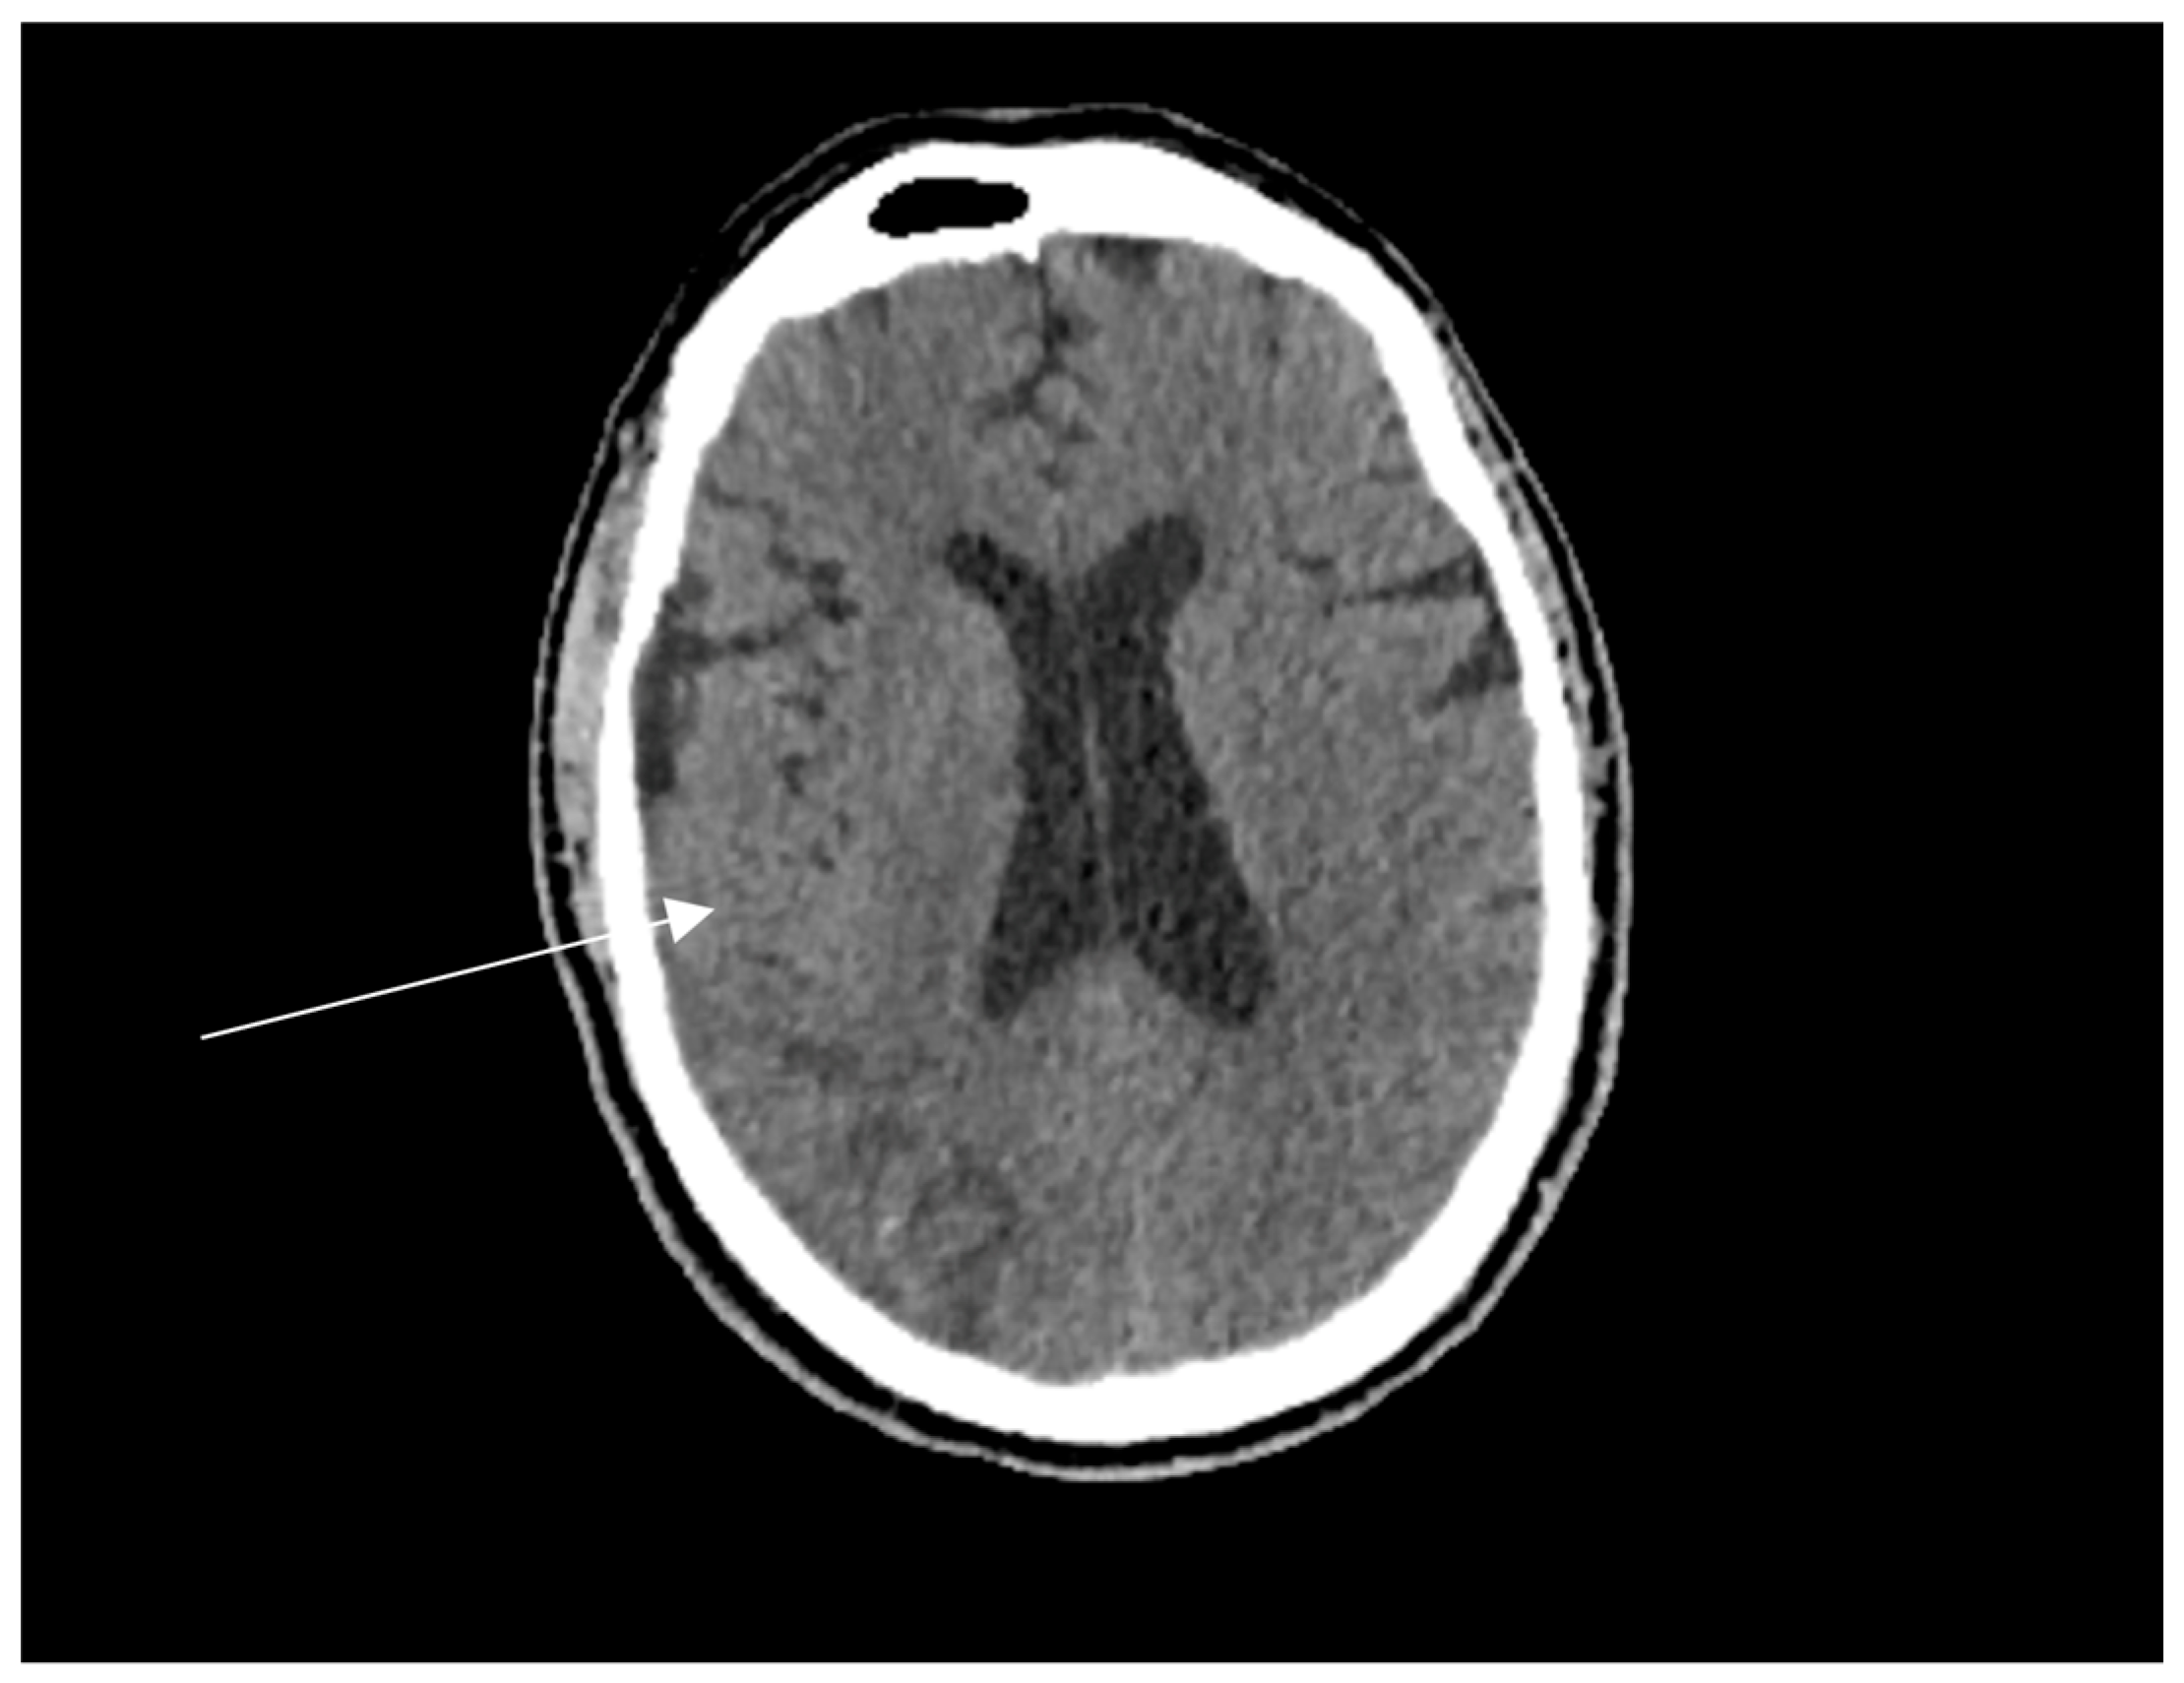

Non-contrast computed tomography (CT) of the head demonstrated an evolving acute infarct in the right posterior parieto-occipital region with poorly defined hypodensity, white matter oedema, and mild mass effect (Figure 1). Apixaban was immediately withheld, and aspirin was commenced after coagulation screening. MRI brain was requested to rule out a space-occupying lesion.

Figure 1. Non-contrast axial Computed Tomography (CT) of the brain showing an evolving infarct in the right posterior parietal lobe (white arrow), characterised by ill-defined hypodensity and loss of grey-white matter differentiation, consistent with acute ischaemic stroke. There is no significant midline shift or haemorrhage noted.